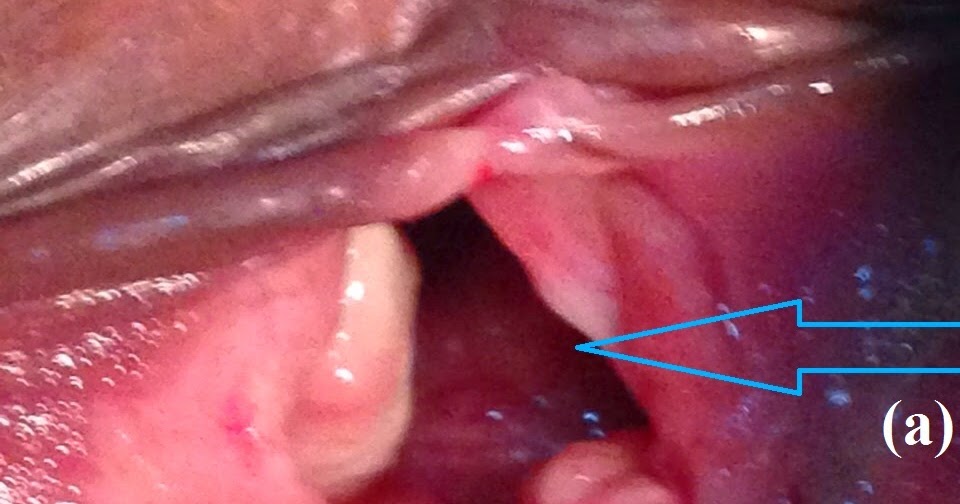

Episiotomy scar granulation tissue 2. Largest and most numerous vaginal granulation tissue on the episiotomy scar reported in the literature. A 34-year-old primipara presented to our clinic complaining of excessive yellowish non-foul-smelling vaginal discharge with no associated vulvar itching on and off since her delivery.

A 34-year-old primipara presented to our clinic complaining of excessive yellowish non-foul-smelling vaginal discharge with no associated vulvar itching on and off since her delivery.

Granulation tissue postpartum. This granulation tissue manifests as an exquisitely painful fibrotic and inflammatory area of scarring at the site of the healing laceration. While the formation of some granulation tissue is a normal component of the wound-healing cascade this tissue may become pathologically excessive and persist in. The presence of granulation tissue can also lead to pain and bleeding with intercourse pelvic exam or the use of tampons.

Granulation tissue is a common cause of postsurgical vaginal bleeding and frequently is biopsied particularly if there are concerns stemming from a prior surgical procedure for a neoplasm. Typically granulation tissue appears as a raised red lobular lesion in. They eventually dissolved but turned into bumpy granulation tissue.